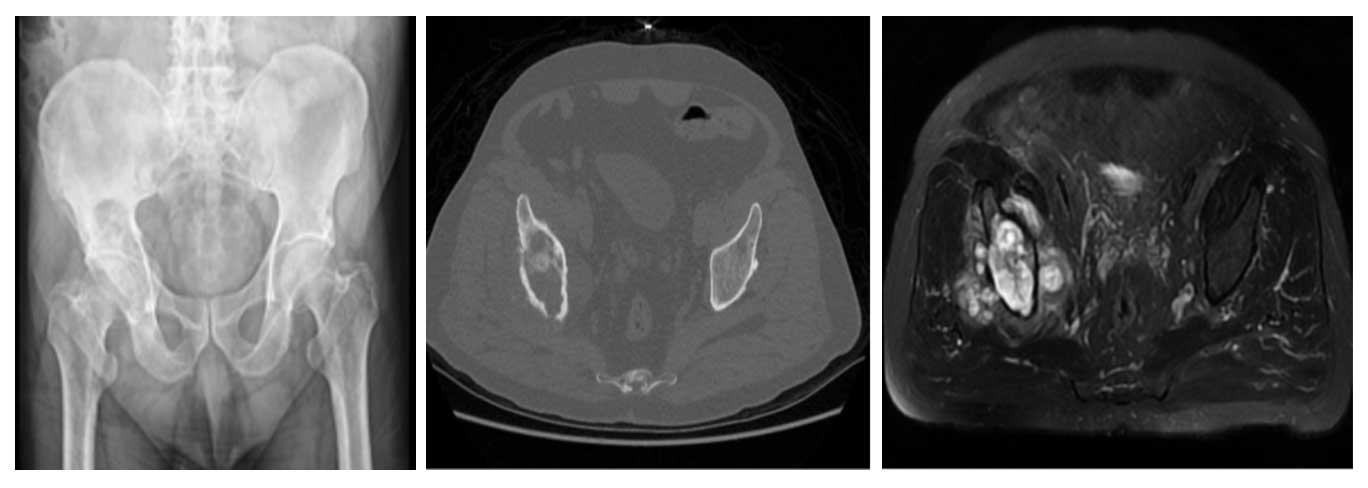

58 yaş erkek hasta, 7 aydır mevcut sağ kalça ağrısı ile başvurmuş, ağrı zamanla artmış ve yürümekte güçlük çekmekteydi. İğne biyopsisi sonucu kondrosarkom tanısı konmuş, taramalarda metastaz saptanmamıştır.

Ameliyat Öncesi: Röntgende iliak kanatta yeniklik, tomografide kemik harabiyeti, MR’da ise yumuşak dokuya uzanan tümör dokusu görülmekte.